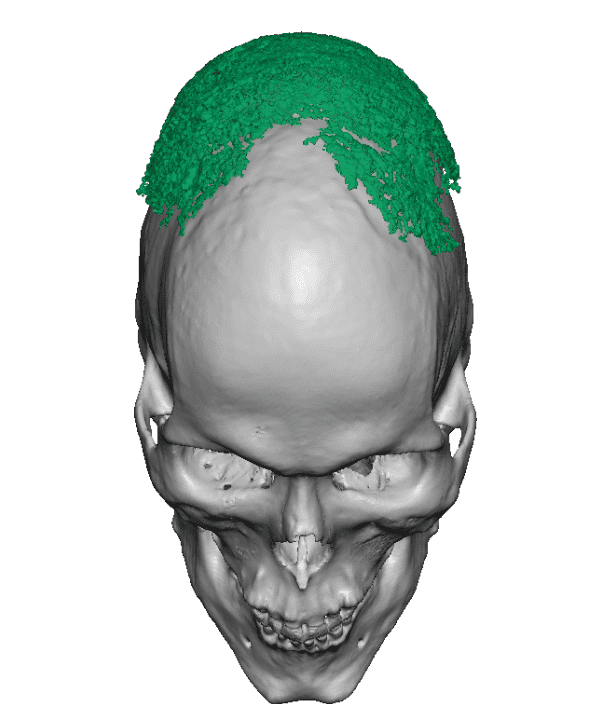

Desire for change of head shape from front view form an inverted V shape to a rounder and wider head shape.

Placement of custom extended forehead-temporal implants through incisions in the crease behind the ear. (he had a prior back of head skull implant which is green in the implant designs and which the head widening implants partially covered it)